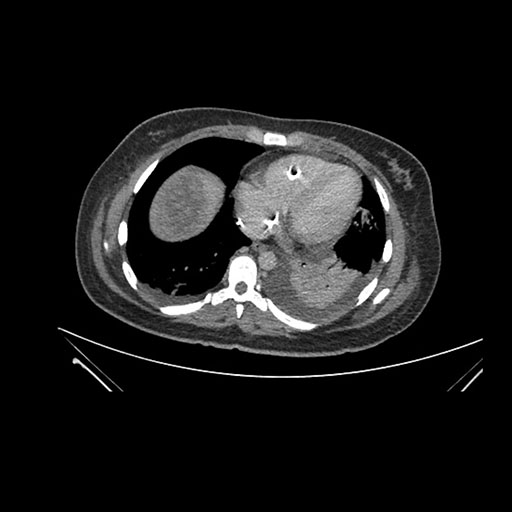

Imaging Analysis

Look through the patient's CT scan to identify any areas of concern for the necessary procedure.

Axial Venous

Based on initial findings, which issue(s) would you be most concerned about?